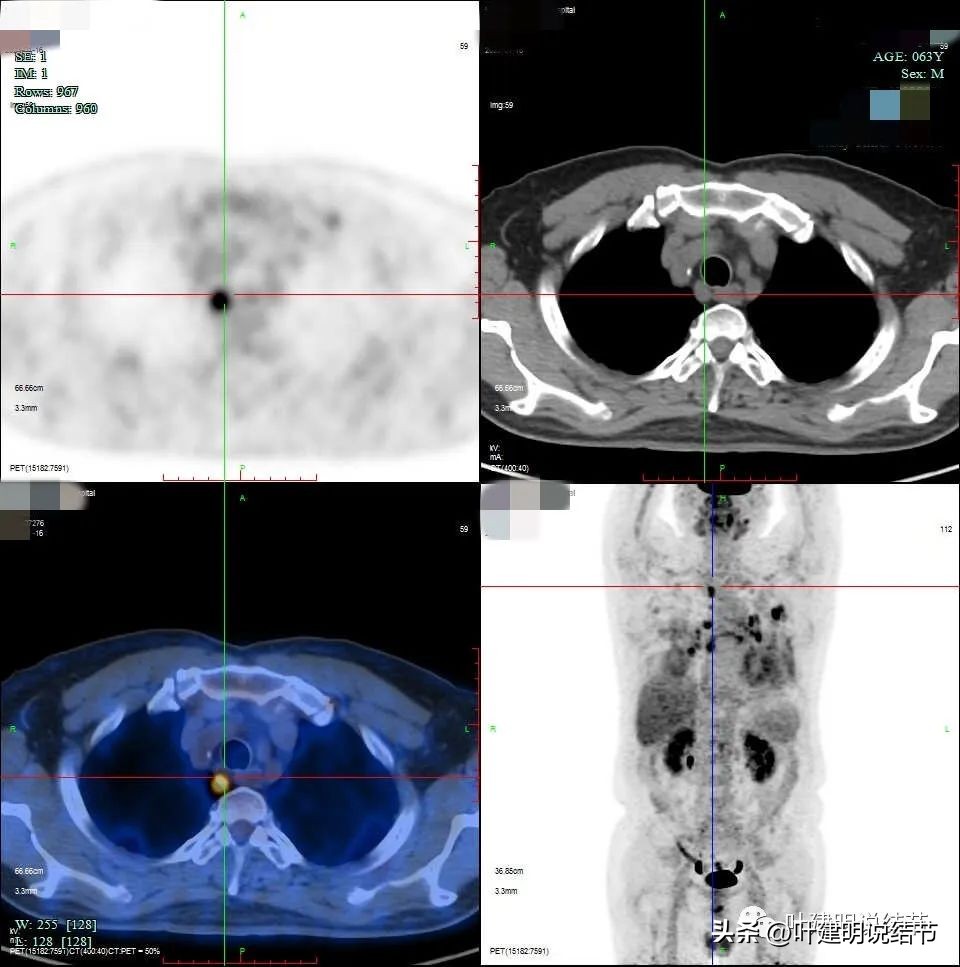

右侧给隔淋巴结

右侧肺门淋巴结

左侧淋巴结

左上病灶虽有钙化,但葡萄糖代谢增高,有诸多恶性影像表现的特征,仍需要考虑恶性可能性大,至少要取得病理以确定或排除肺癌。肺门与纵隔淋巴结的肿大与葡萄糖代谢高摄取,结合两肺炎性改变的表现,以及肿瘤的生物学行为,转移不容易解释,炎性的容易解释。